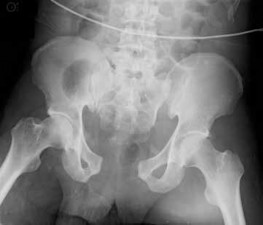

Figure 7Figure 7 is the pelvic radiograph of a 33-year-old man involved in a high-speed automobile crash. Examination reveals a blood pressure of 90/50 mm Hg and a pulse rate of 120/min. Radiographs of the chest and lateral cervical spine are normal. A CT scan of the abdomen does not reveal any intraabdominal bleeding. What is the most appropriate management for the pelvic fracture?